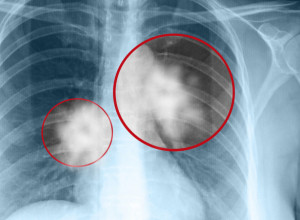

Gore od cigareta: Jedna svakodnevna navika je kobna po zdravlje, može da poveća rizik od bolesti pamćenja